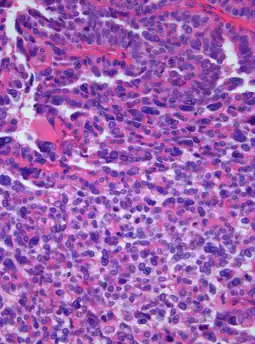

| Photomicrograph of hematoxylin-eosin stained section of a choroid plexus carcinoma (grade III WHO) at 400x magnification. | |